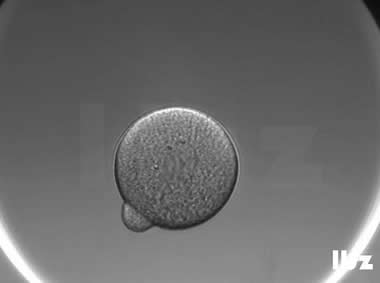

| |

| 卵裂球碎裂:受精卵在第一次卵裂阶段就直接碎裂为大小不一的碎片。 | |